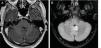

Results40 patients were included. The range age was 36–80 years. The most frequent reason for request the MRI was hearing loss (52.5%). Neuroradiologist without IVC found 82.5% of extraotic pathology and 17.5% of otic pathology, highlighting the neurinoma of the VIII pair (7.5%); ossifying labyrinthitis, retrofenestrated otosclerosis and cholesteatoma. After IVC administration, findings were similar. The resident identified otic pathology in 5% in baseline sequences and 20% using CIV. The interobserver correlation using IVC was excellent (0.97), but weak without IVC (0.52). There was a correlation between the reasons for request the MRI and the findings in the ears, both in protocols without IVC (p=0.004) and in protocols with IVC (p=0.002).

ResultadosSe incluyeron 40 pacientes. El rango de edad fue de 36-80 años. El motivo de solicitud más frecuente fue hipoacusia (52,5%). El neurorradiólogo sin CIV encontró un 82,5% de patología extraótica y un 17,5% de patología ótica, entre las que destacaba un neurinoma del VIII par (7,5%); también laberintitis osificante, otosclerosis retrofenestrada y colesteatoma. Tras la administración de CIV, los hallazgos fueron similares. El residente identificó patología ótica en el 5% en las secuencias basales y un 20% usando CIV. La correlación interobservador usando CIV fue excelente (0,97), pero débil sin CIV (0,52). Existió correlación entre los motivos de solicitud y los hallazgos en los oídos, tanto en los protocolos sin CIV (p = 0,004) como en los protocolos con CIV (p = 0,002).